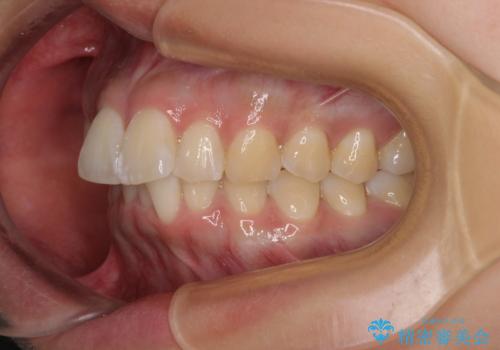

前に飛び出して目立っている前歯を整える インビザライン矯正治療

- 前方に主張した前歯2本を気にして来院された患者様です。

下顎前歯がデコボコしており、その影響で上顎前歯が前方に押し出されている状態でした。

口元が閉じにくいという印象はなかったため、非抜歯矯正にて歯列を整えていくこととしました。

上下左右の親知らずを抜歯し、上下ともに歯列を後方と側方に拡大し、口元を突出させることなくデコボコを解消することとしました。

前歯の形が台形であり、歯列が整ったところでブラックトライアングルが目立つ仕上がりとなったため、IPR(歯と歯の間を削る処置)によって歯の形態を修正し、隙間の目立たない歯列に仕上げることができました。